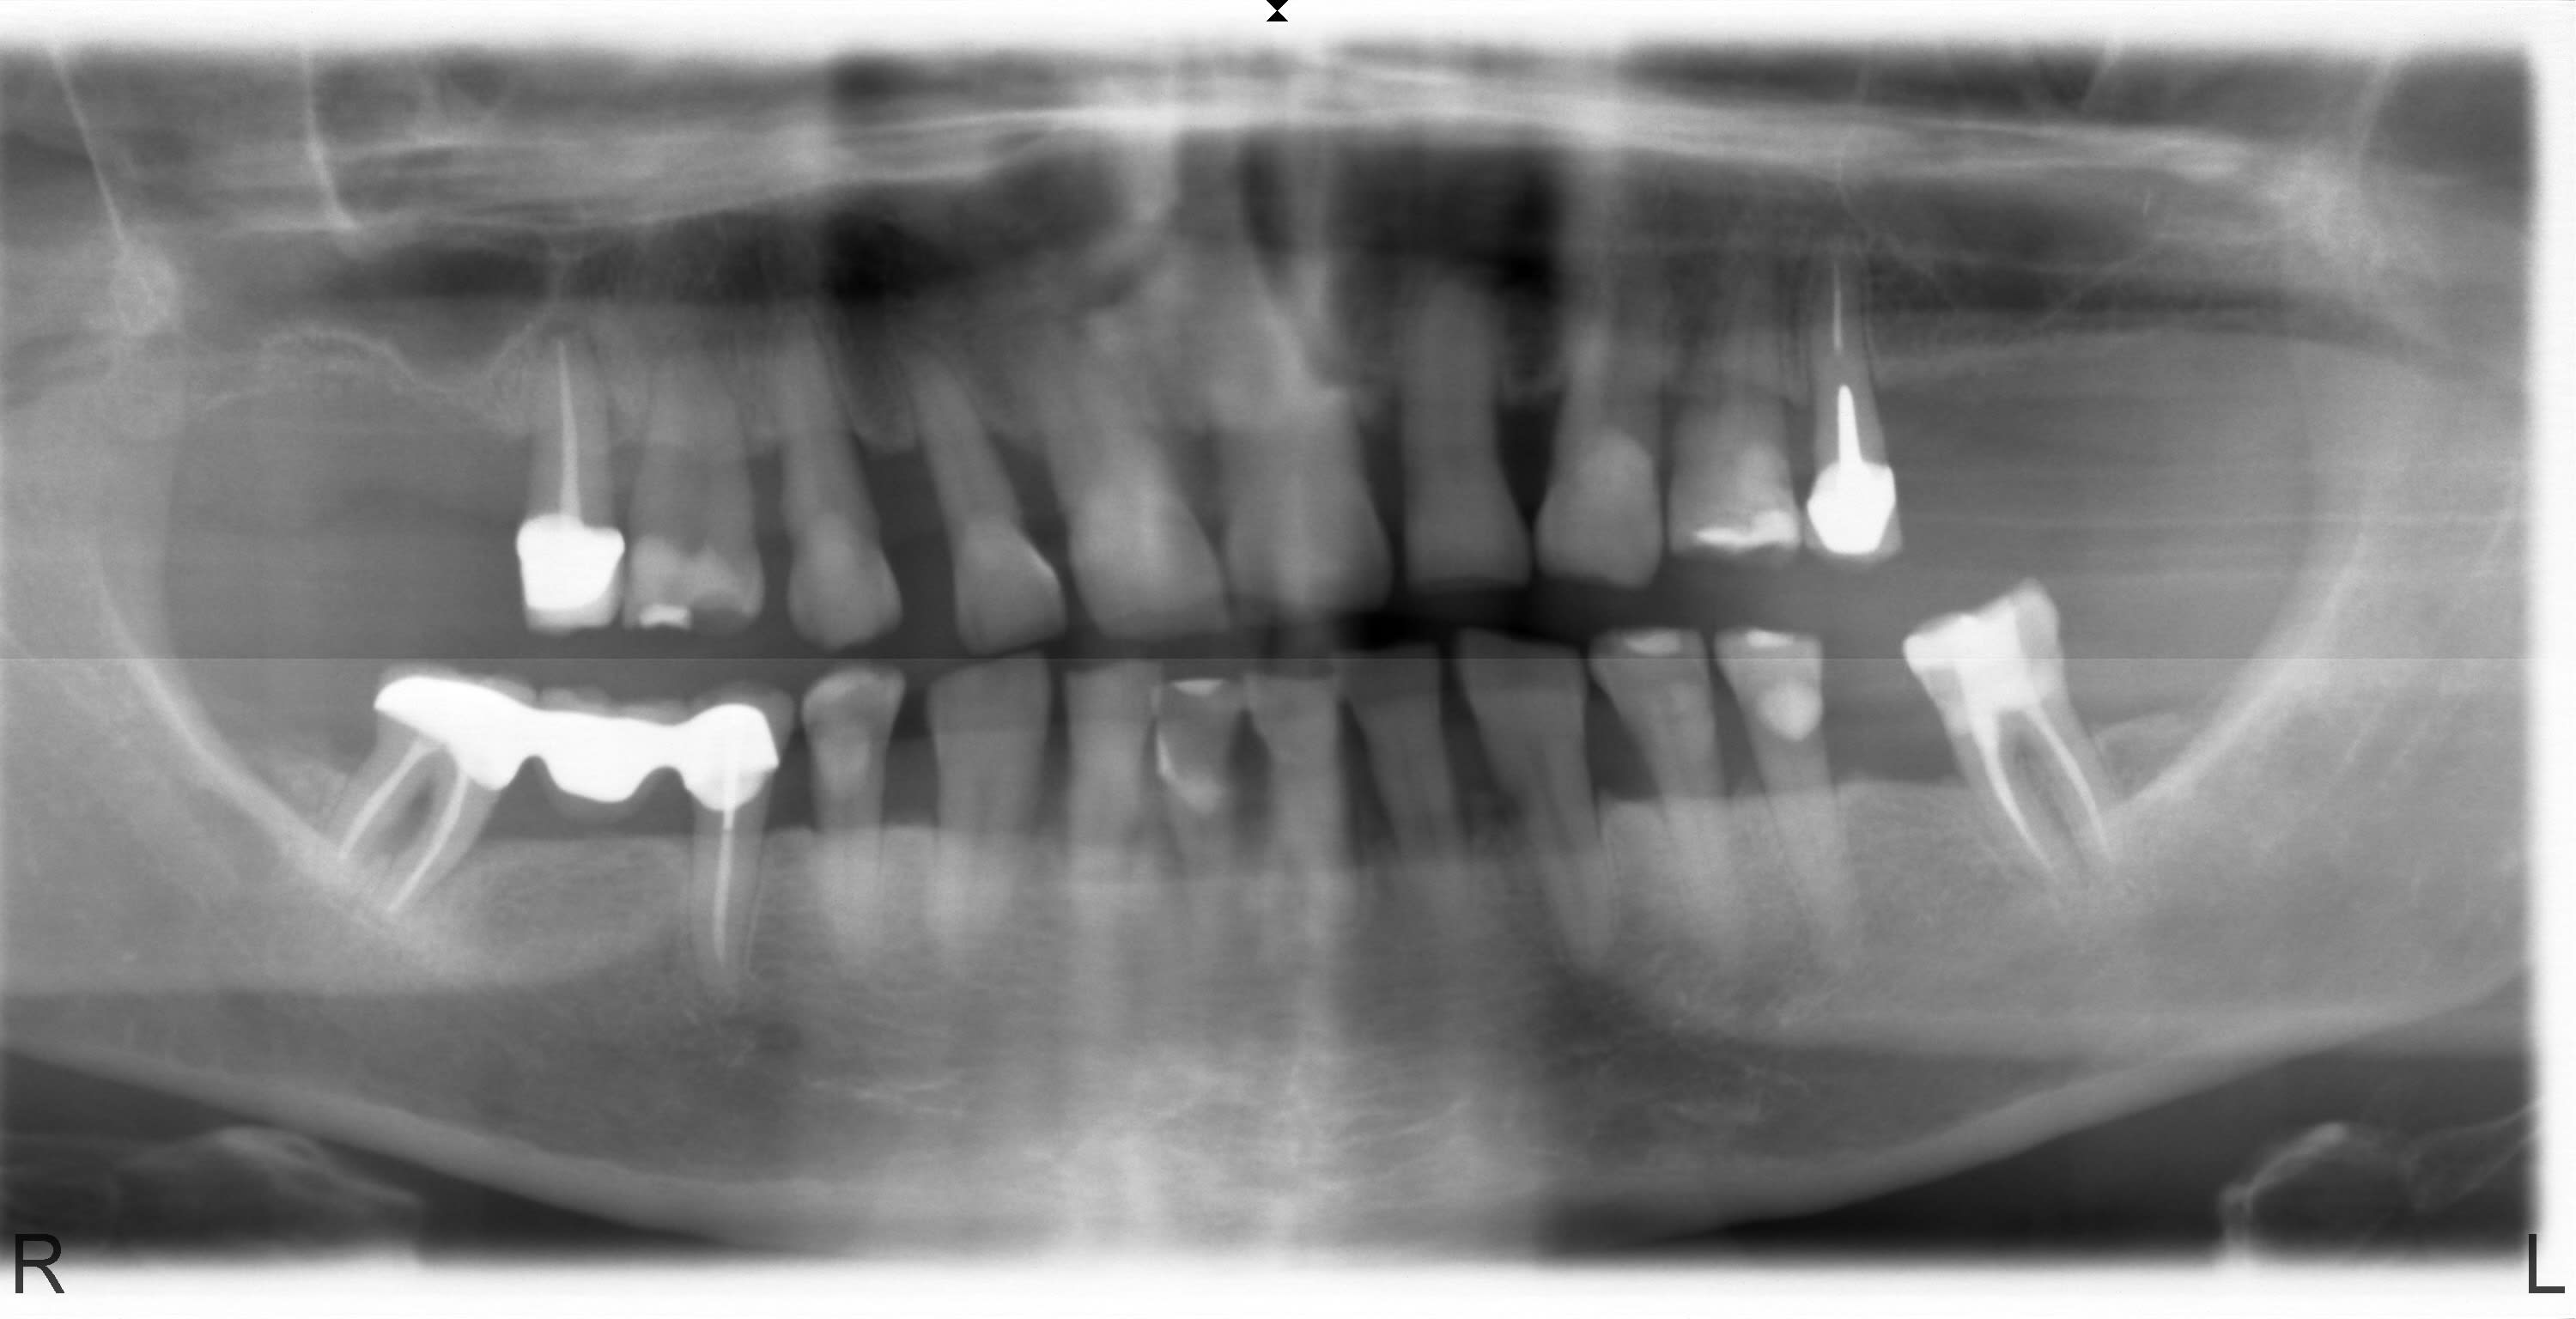

Je vous joins la panoramique. Que pensez vous de l'idée de réaliser un bridge complet pour solidariser les dents et "masquer" les mobilités ? Oui je sais que c'est reculer pour mieux sauter mais peut être moins invasif que extraction de tout ce qui reste pour implanter d'autant plus que les moyens ne sont pas au RDV plus antécédent de rejet de greffe au niveau du secteur 1.

Faut expliquer que ça peut foirer, mais au vu de la pano... ( cad de pas grand chose point de vue informations) ça semble possible.